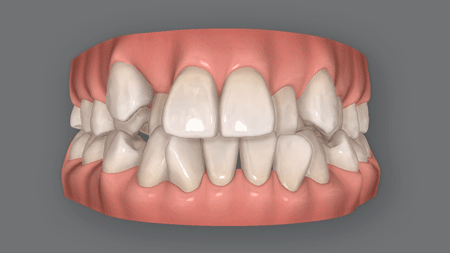

受け口の原因と失敗例

(2) 下あごがずれている

下あごが前にずれて受け口

口呼吸や噛み合わせの問題、あるいは遺伝的な要因で上あごに対して下あごが前にずれると、受け口になってしまいます。

下図のように、下あごが全体的に前に出てしまったため受け口になってしまった、という状態です。

なお、遺伝的に骨格に問題があって下あごがずれている場合は、手術が必要になることもあります。